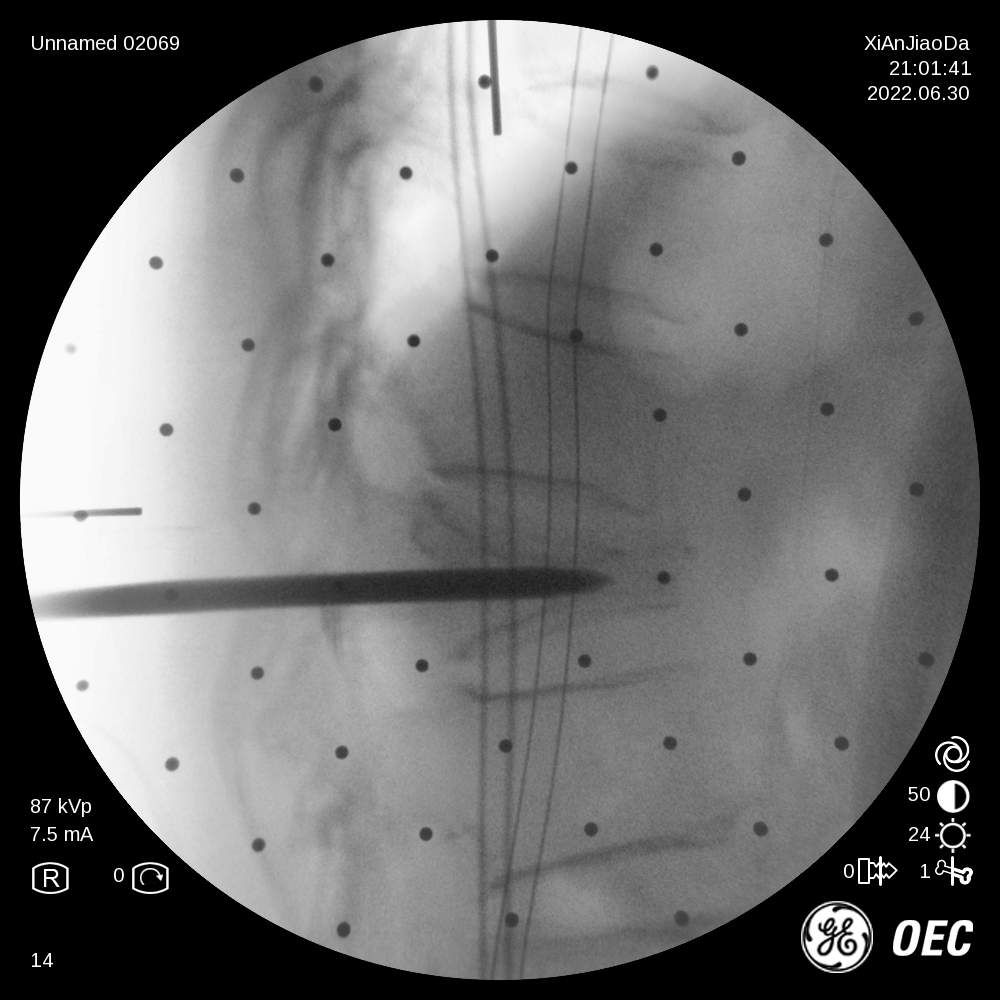

在该机器人辅助手术过程中,仅需通过正侧位进行伤椎识别,通过软件将正侧位透视图与术前规划数据的结合,即可得到病人伤椎的姿态以及实际的穿刺角度,之后机械臂根据软件参数进行精准定位,手术医生在机械臂引导下一次性进针成功,并对进针位置角度表示满意,整个过程少于20分钟,实现了手术的更精准化、高效化。相较于传统定位流程,术前规划只能保存在医生脑海中,术前与术中流程无法很好的衔接,术中穿刺依赖医生丰富的经验,对于情况复杂的病人,术中需要反复试验,导致手术时间延长、患者受辐射量增加。后续放置球囊、注入骨水泥等操作则同传统手工操作。